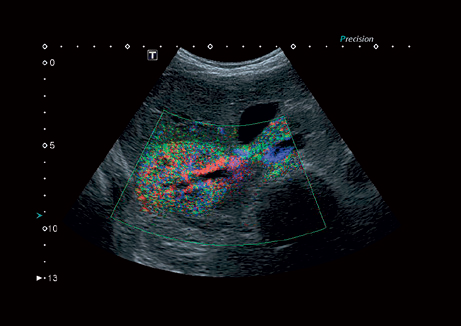

• Precision Imaging - технология получения изображений мелких деталей с четко очерченными границами и высокой однородностью

Precision Imaging:

Да

• Прецизионная визуализация (Precision Imaging) для послойного дифференцирования тканевых структур и высокой детализации;